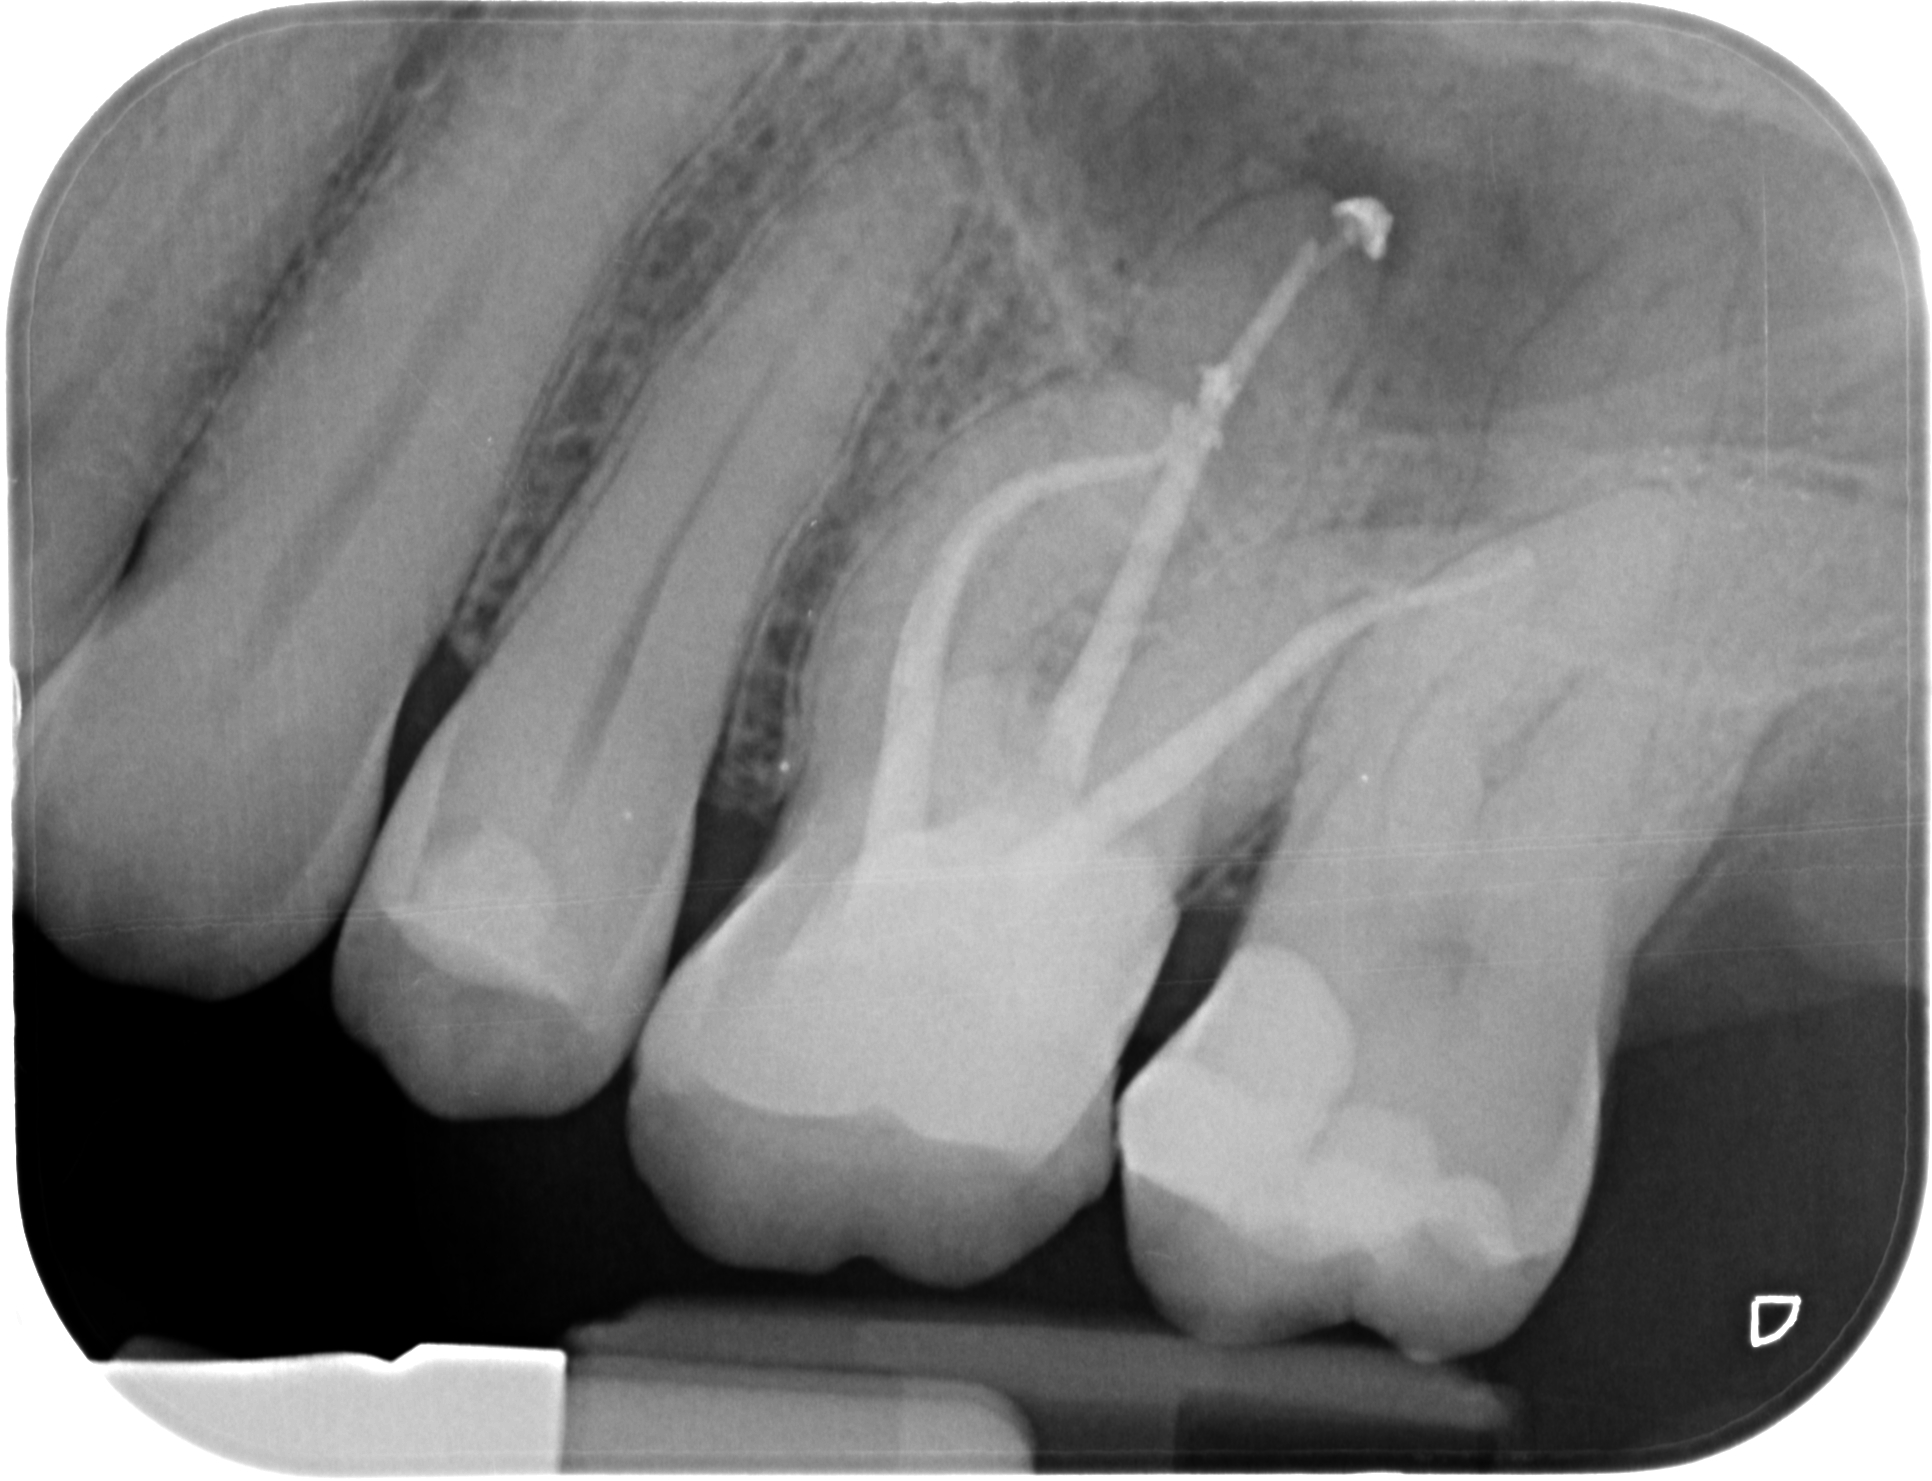

La Endodoncia es la especialidad que permite conservar el diente en boca cuando la patología pulpar del diente es ya irreversible.

Durante una endodoncia, vulgarmente conocida como “matar el nervio”, lo que hacemos es eliminar el tejido pulpar (el nervio) enfermo y conformar y desinfectar todo el sistema de conductos radiculares, para luego rellenar y sellar esos conductos de un material termoplástico. A continuación hay que Reconstruir la corona mediante técnicas adhesivas, bien con composite o si la reconstrucción es muy grande, recurrimos a la Porcelana como mejor material para restituir la integridad funcional y anatómica perdida.